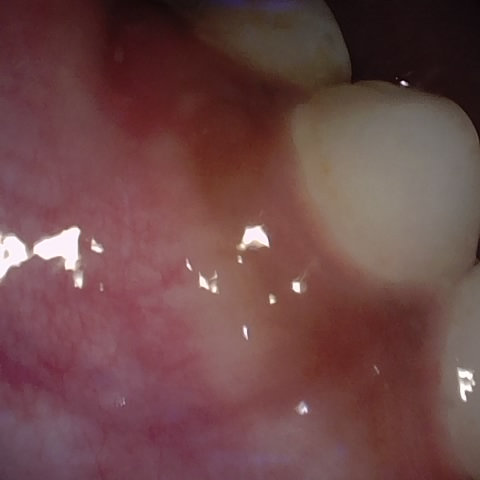

NHD39174

Annotated as "Good"

Original Image Rendering Image